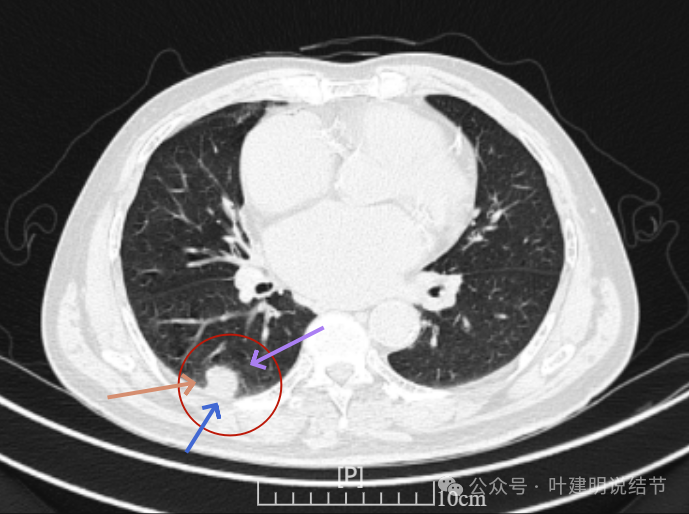

再看2024年6月时的影像:

右下新增病灶,混合密度,整体轮廓较清,瘤肺边界欠清。

有小血管进入,边缘毛糙。

局部有毛刺,但不够锐利;病灶感觉有一层晕似的,邻近胸膜下也有淡磨玻璃影。

实性密度为主,周围少许很淡的磨玻璃影。

边缘不平有毛刺,但不锐利;贴着胸膜但无明显牵拉。局部表面有浅分叶似的,但总体膨胀感不够。

病灶表面不光滑,边上有晕,邻近有淡磨,贴着胸膜无牵拉。

病灶边缘欠清晰,瘤肺边界稍模糊。较宽的基底贴着胸膜。